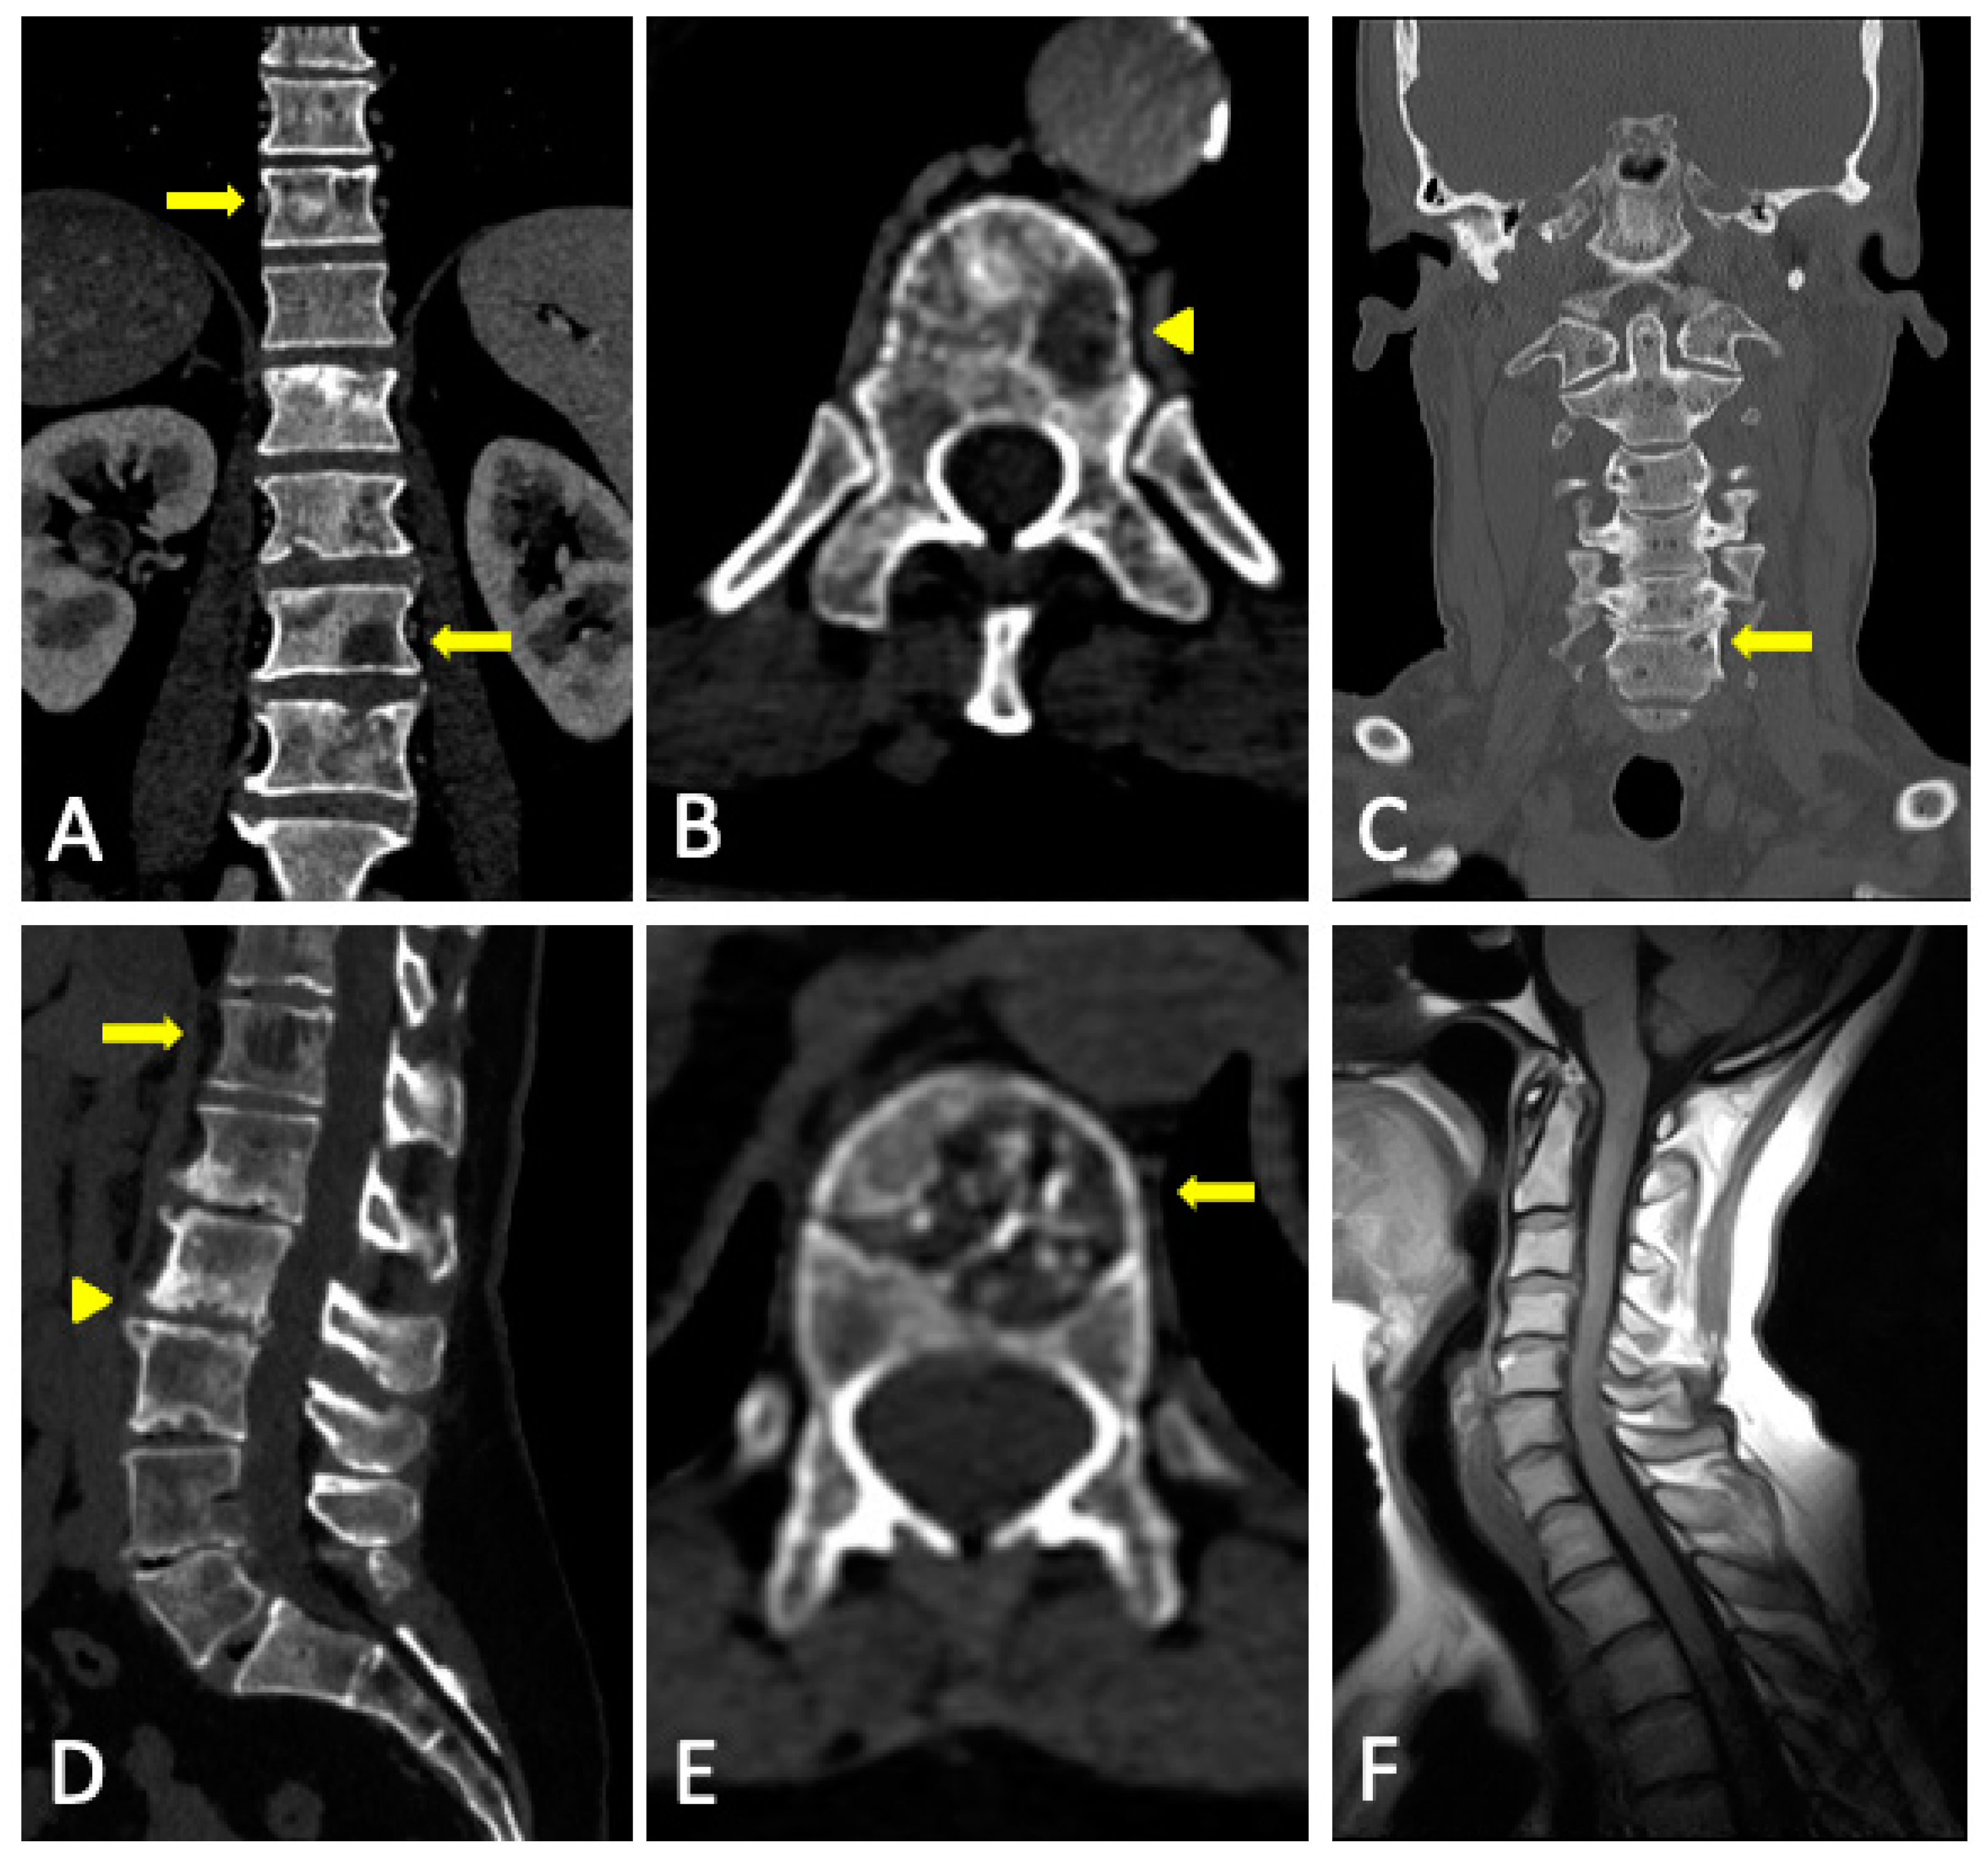

- Diffuse pattern: Diffuse disease can be suspected from a diffuse decreased signal on T1WI (either iso- or hypointense to intervertebral discs and muscle) and a diffuse increased signal throughout the marrow on T2FSWI, STIR, or high b-value DWI. Marrow ADC values above 600–700 μm2/s in a nontreated and newly diagnosed patient with MM could be used to increase confidence for the diagnosis of diffuse marrow involvement [33] (Figure 7). Due to potential false-positive findings, diffuse disease in imaging must be supported by bone marrow trephine biopsy [26].